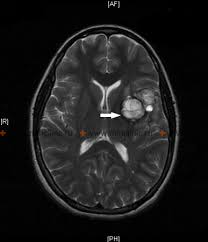

Partial seizures (also called focal seizures and localized seizures) are seizures which affect only a part of the brain at onset. The brain is divided into two hemispheres, each consisting of four lobes - the frontal, temporal, parietal and occipital lobes. In partial seizures the seizure is generated in and affects just one part of the brain - the whole hemisphere or part of a lobe. Symptoms will vary according to where the seizure occurs. In the frontal lobe symptoms may include a wave-like sensation in the head; in the temporal lobe, a feeling of déjà vu; in the parietal lobe, a numbness or tingling; and in the occipital lobe, visual disturbance or hallucination. Partial seizures are split into two main categories; simple partial seizures and complex partial seizures. A new classification system for partial seizures has been described in the 18th Edition of Harrison's Principles of Internal Medicine. The new classification splits partial seizures into "partial seizures with dyscognitive features" and "partial seizures without dyscognitive features".